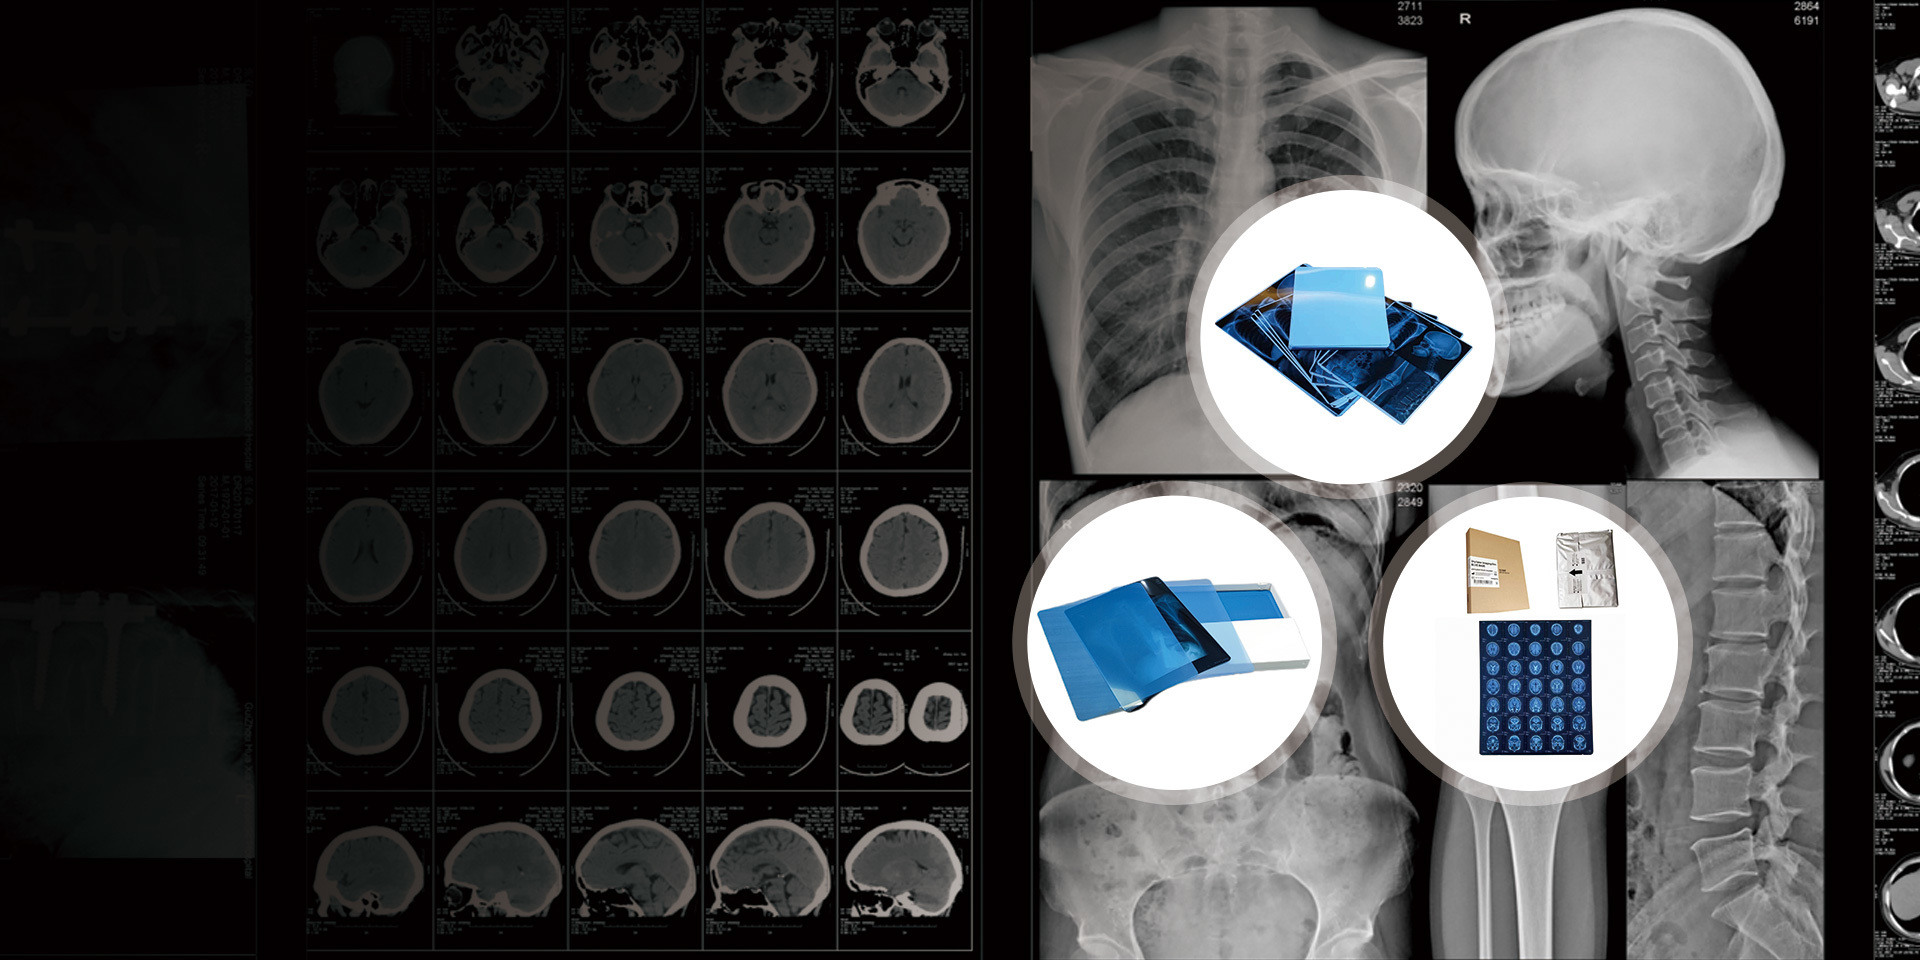

Our Product Series

Independently develops and produces thermal film, medical laser film, and medical printing Film and other products.

As an indispensable and important tool in the medical diagnosis process, medical film plays a crucial role in disease detection, diagnosis, and treatment tracking.

Common types include X-ray films, CT films, and MRI films. X-ray films are used for general radiography, while CT and MRI films display detailed cross-sectional images of the body, aiding in accurate diagnosis and treatment planning.